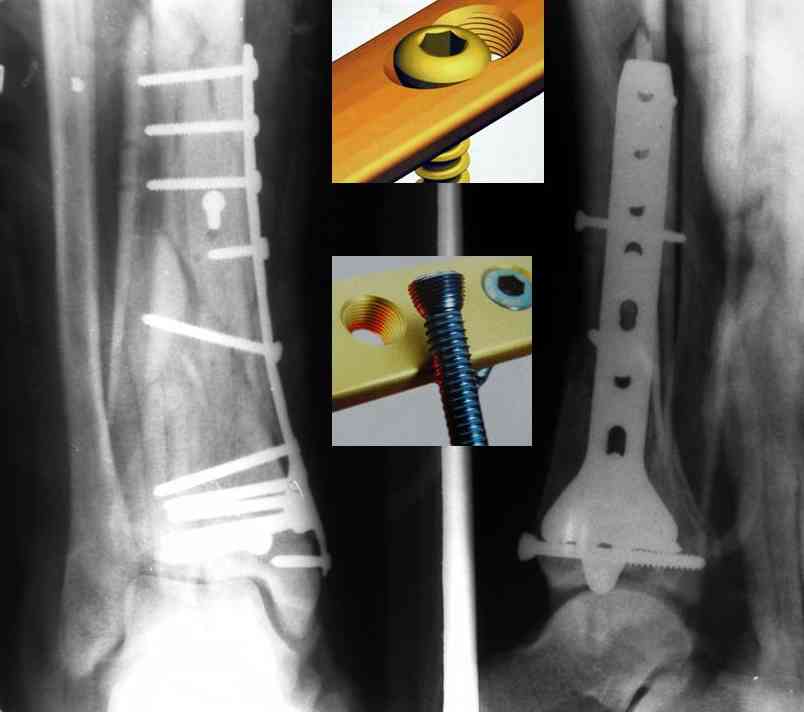

Кстати, при переломах переднего края по классификации АО В-3 при переломах пилона пластина укладывается по передней поверхности. Она достаточно тонкая и эластичная, не надо этого бояться. Посылаю три снимка.

|